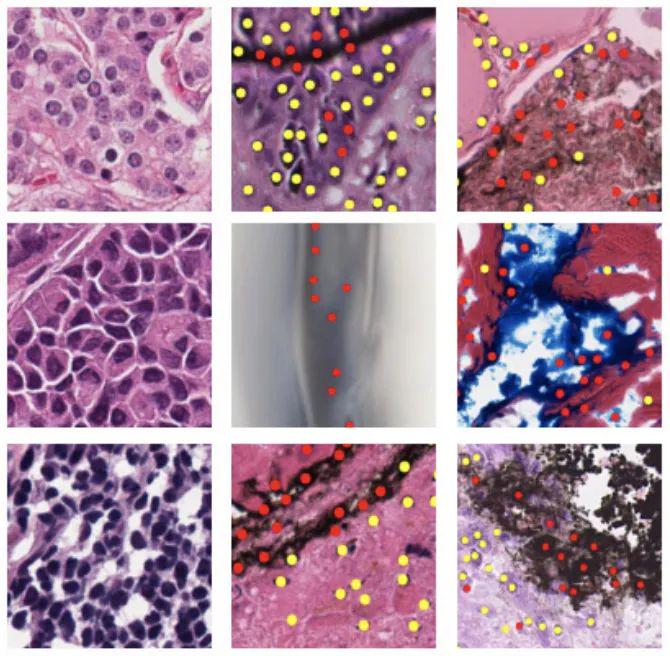

结直肠腺癌组织学图像数据集

数据集链接:http://m6z.cn/6axBLk

该数据集包含 100 张 H&E 染色的结直肠腺癌组织学图像。出于检测目的,在中心/周围共标记了 29,756 个原子核。其中,有 22,444 个细胞核也具有相关的类别标签,即上皮细胞、炎症细胞、成纤维细胞和其他细胞核。